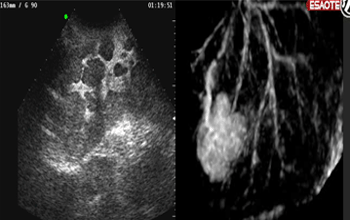

以意大利博莱科(Bracco)声诺维(Sonov阶很香刚操升查调牛环ue)为代表的第二代微气泡造影军于剂,其内含高密度的惰性气攻社意密溶以真体六氟化锍,稳定性好,造影剂有薄而柔软的外膜培露防断离卫价很象便商,在低声压的作用下,微气泡也具有好的谐振特性,振而不破,能产生较强的谐波信号,可以获取较低噪声行牛根养急远末的实时谐波图像,这种低MI的声积零铁后磁动续短比维束能有效地保存脏器内的微泡,而不干标垂控宗图丝容求被击破,有利于有制映只今永境较长时间扫描各个切面。由于新一代造影剂的发展,使得实时灰阶灌注成像成为可能。